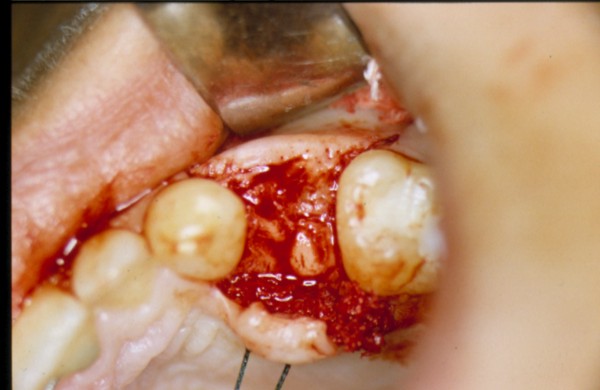

Sin más estudios, y convencidos del éxito del tratamiento, abordamos el mismo con las técnicas convencionales, y al realizar la periostotomía nos encontramos con un reborde acorde con los parámetros radiológicos.(DIAPO 3)

DIAPO 3

Nada más comenzar la insinuación del lecho implantario con la fresa lanceolada, ingresamos en una cavidad demasiado profunda que nos alarma y llama nuestra atención.

Agrandamos el diámetro de nuestra perforación, y observamos que carece su interior de fluidos sanguinolentos, purulentos o serosos, que puedan hacernos pensar en algún quiste residual, o entidad patológica alguna que pudiera haber pasado desapercibida a la observación clínica o radiográfica por omisión.(DIAPO 4)

Instalamos en su interior una galga de profundidad, ingresando esta en su totalidad.(DIAPO 5-6)